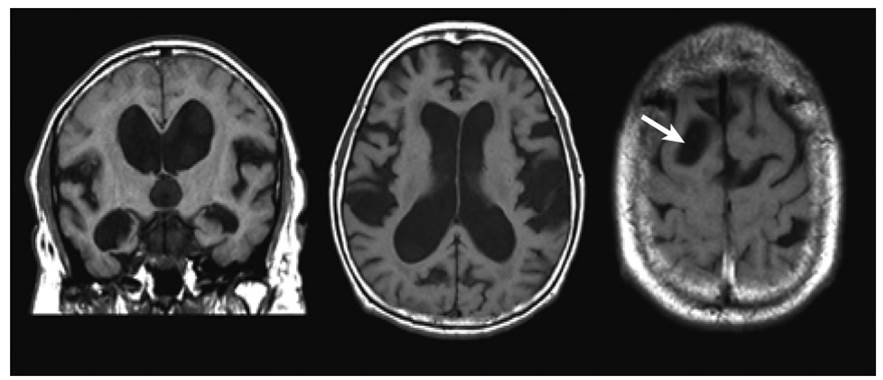

DESH Dilated epidural spaces in hydrocephalus

Transependymal oedema